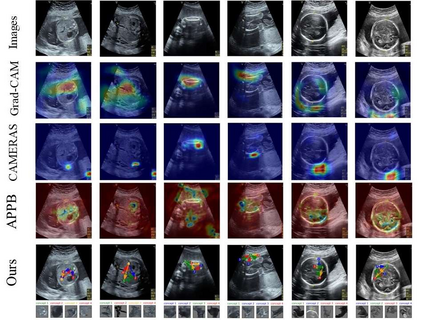

Although deep neural networks (DNN) have achieved state-of-the-art performance in various fields, some unexpected errors are often found in the neural network, which is very dangerous for some tasks requiring high reliability and high security. The non-transparency and unexplainably of Convolutional Neural Networks (CNN) still limit its application in many fields, such as medical care and finance. Despite current studies that have been committed to visualizing the decision process of DNN, most of these methods focus on the low level and do not take into account the prior knowledge of medicine. In this work, we propose an interpretable framework based on key medical concepts, enabling CNN to explain from the perspective of doctors' cognition. We propose an interpretable automatic recognition framework for the ultrasonic standard plane, which uses a concept-based graph convolutional neural network to construct the relationships between key medical concepts, to obtain an interpretation consistent with a doctor's cognition. Extensive experiments have empirically shown that our model can meaningfully explain the decision of the classifier and provide quantitative support.